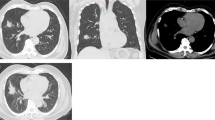

In addition, a new conserved restriction pattern specific for M. mucogenicum was identified in eight cases (Figure 1a, b). This subspecies had not been considered in the work of Cook et al.5 Homology matches of the sequenced PCR products (NCBI database) demonstrated a concordance of 93–100% with the reference sequence of M. mucogenicum (Table 4). Multiple alignments demonstrated sequence variants (sequevars) showing a divergence in up to 7 bp of the eight M. mucogenicum cases. Despite the existence of sequevars, species identification by RFLP was possible in all of the M. mucogenicum cases, since restriction sites were conserved.

(a) A new restriction pattern for M. mucogenicum was observed by using RFLP on PCR products (hsp65 amplification) in eight cases. The agarose gel shows a comparison of the specific restriction pattern found for DNA of M. mucogenicum to the restriction pattern of control DNA derived from M. tuberculosis complex. Sizes of restriction fragments of M. mucogenicum: H: 133 bp (uncut), b: 124+9 bp, M: 85+31+18 bp. SM, size marker (Hae3 digest of Phi × 174). Restriction enzymes: H, HhaI; B, BstuI; M, MboI. (b) Conserved DNA sequence of the amplified hsp65 fragment of M. mucogenicum, which was found in three of eight cases (Table 4). Restriction sites are indicated in triangles, primer binding sites are shown in italics.